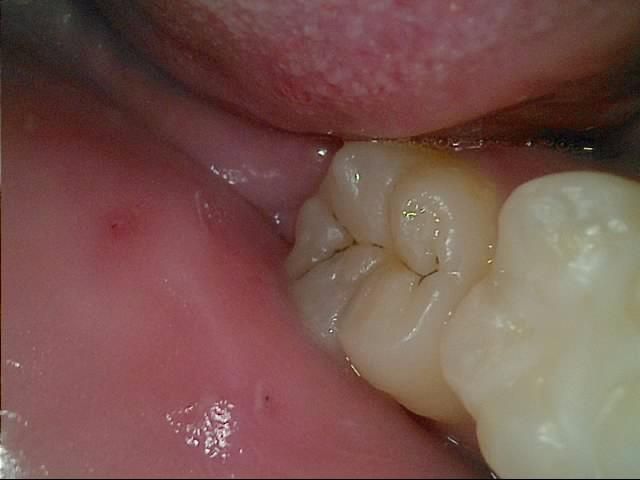

사진속 구강상태에서 초기 정지우식이라고합니다. 근데 재광화가풀려 며칠동안 조금이라도 정지우식이 다시 진행되었다면, 진행된지 고작 2주정도 지났다고 쳐도 인레이가 필요한치아가 있나요? 많이 진행되지않고 2주동안 이제막 충치가번지기 시작하는경우, 레진인지 인레이인지 궁금합니다

• 1번 째 사진